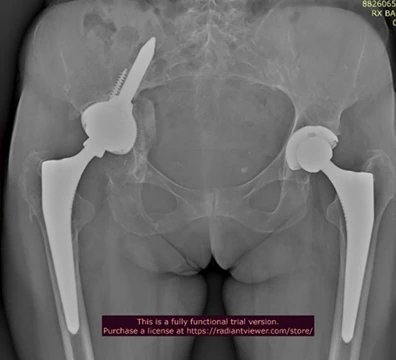

Tecniche di Ricostruzione Femorale

Per il femore, la stabilità si ottiene cercando l’ancoraggio distale dove l’osso è ancora solido:

- Steli da Revisione Modulari: Protesi composte da più componenti che il chirurgo assembla “su misura” durante l’intervento per adattarsi alla forma residua del femore.

- Ancoraggio Distale: Se la parte superiore del femore è riassorbita e troppo fragile, si utilizzano steli lunghi conici che si avvalgono e sfruttano la stabilità conico-diafisaria distale.

A tale proposito ho sviluppato in collaborazione con Medacta, nota e azienda Svizzera molto attiva in campo ortopedico e aperta alle innovazioni tecnologiche, un nuovo impianto specifico per la chirurgia di revisione acetabolare progettato per affrontare i casi più complessi di difetto osseo sfruttando per la stabilità meccanica l’osso iliaco.

- Vite Polare: è l’innovazione tecnologica peculiare che consente di massimizzare la stabilità primaria ancorandosi saldamente entro l’osso iliaco solitamente presente anche nei casi più gravi di difetto osseo.

- Concetto vecchio, disegno moderna: La vite iliaca funge da vero e proprio “pilastro”, trasferendo il carico meccanico direttamente nella colonna posteriore/superiore del bacino, entro l’osso iliaco, bypassando le zone di osteolisi e il difetto cavitario/segmentario dell’acetabolo.